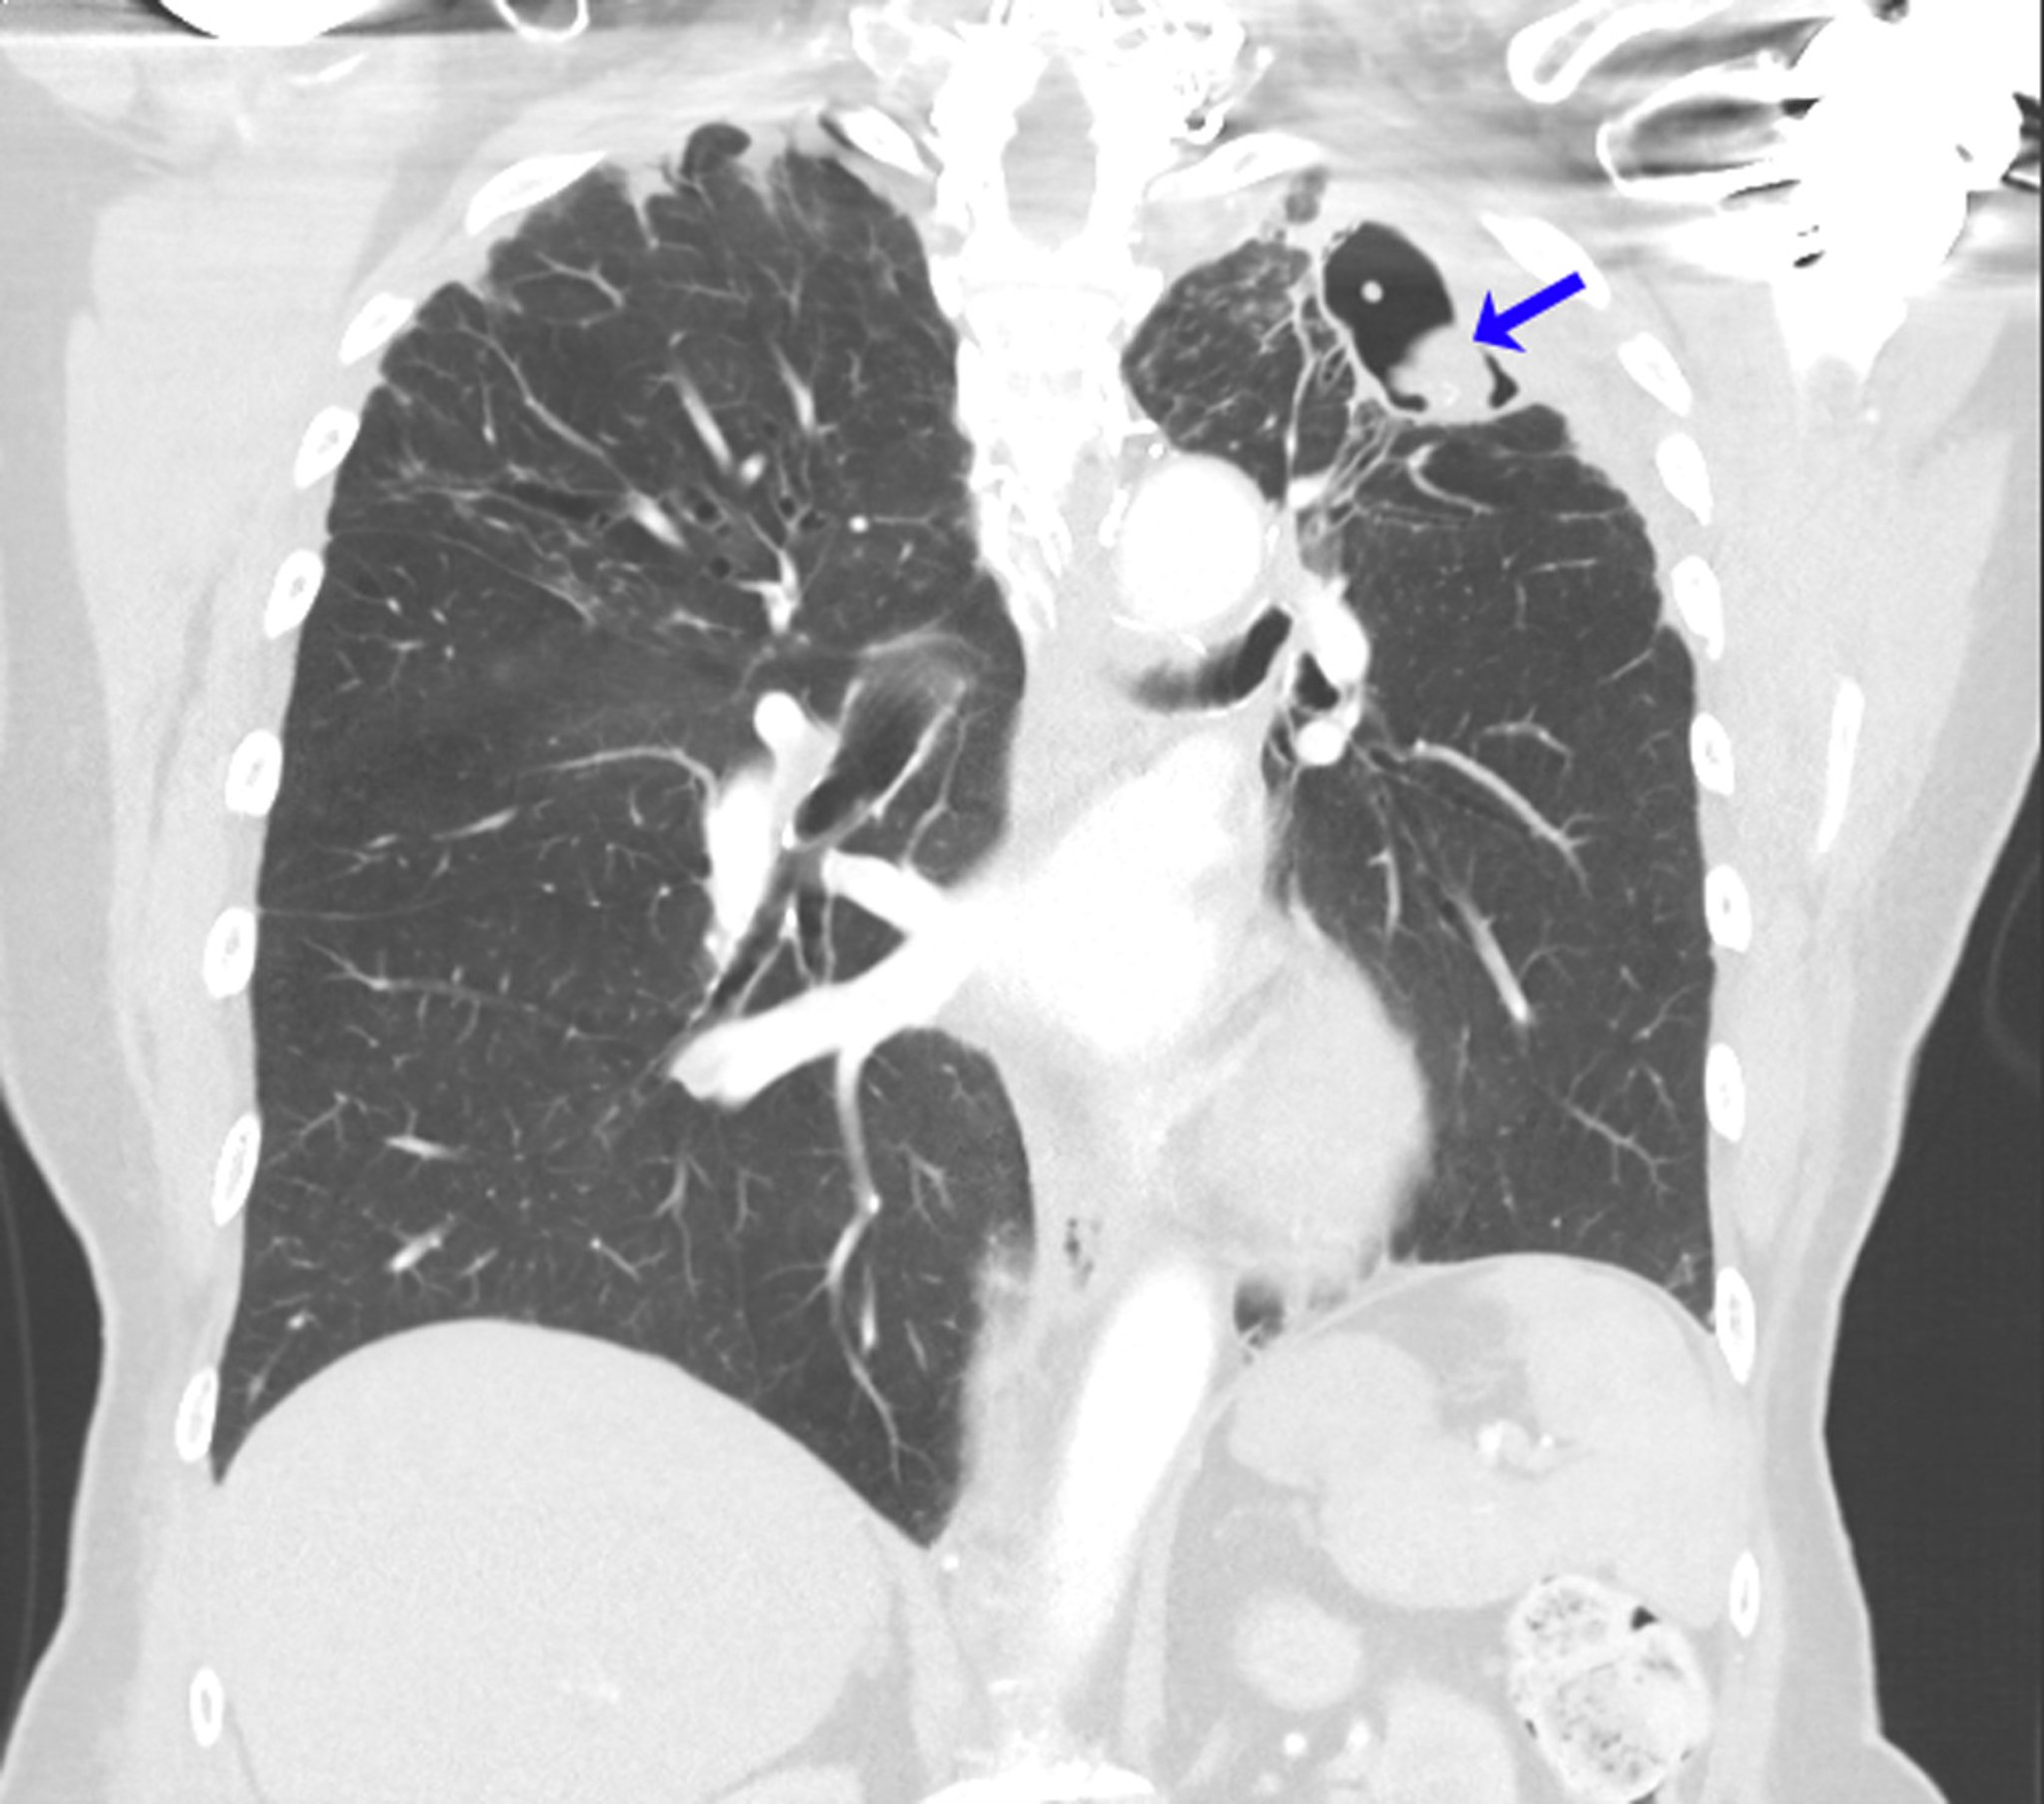

This CT scan shows the lungs of a person with a history of allergic bronchopulmonary aspergillosis in the setting of asthma. After left upper lobectomy for aspergilloma, recurrent mycetoma developed at the left lung apex (arrow).

Image courtesy of Paschalis Vergidis, MD, MSc.